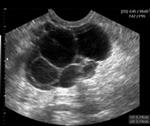

Sebagian besar kista ?hadir? tanpa gejala. Seringkali diketahui secara kebetulan saat pemeriksaan dokter. Rasa sakit yang kuat baru terasa bila kista mengalami komplikasi seperti terpelintir atau pecah.... read more